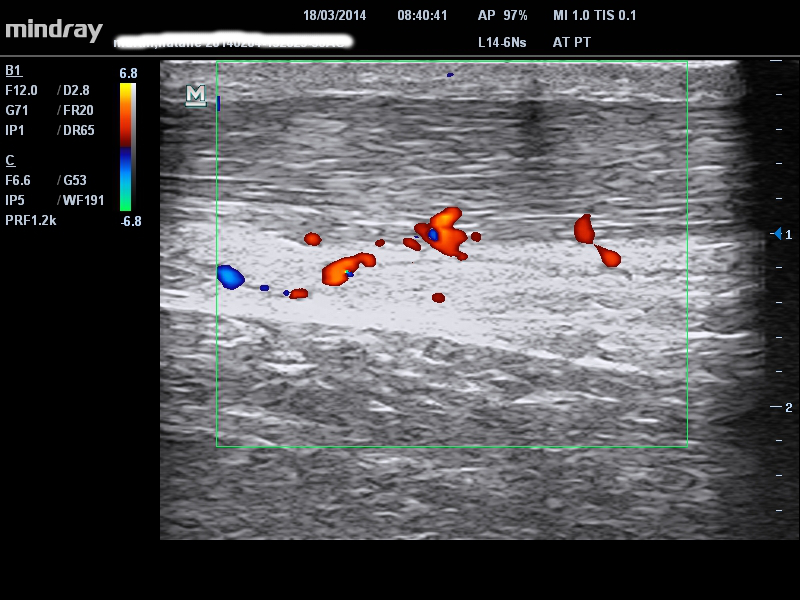

BURSITIS RETROCALCÁNEA

La bursitis retrocalcánea puede presentarse con síntomas que se ubican exactamente en el mismo lugar que la tendinopatía inserciones, pero pueden ser más difusos. Una de las claves para diferenciarlos es el dolor irritable y los síntomas en actividades de baja carga, tales como las elevaciones de talones o la compresión al final del rango de movimiento en la dorsiflexión.

Estos síntomas también presentarse en la tendinopatía por inserción, si es reactiva o irritable es donde el ultrasonido es muy útil. La palpación diferencial de los dos tejidos también puede ser muy útil. Si hay una gran cantidad de líquido o engrosamiento de la bursa en las imágenes, es muy probable que sea un generador de dolor y deba tratarse. Por el contrario, en poblaciones activas un poco de líquido en las imágenes es normal. Nuestro paciente en la imagen a continuación tenía patologías de inserción del tendón de Aquiles y bursa, y síntomas típicos de la bursa, incluso dolorosos en actividades de baja carga y estiramiento. Entonces, tratar la bursitis es una prioridad más allá del tendón. Esta señora había sido diagnosticada y tratada erróneamente dado que la lesión del tendón y la bursitis eran el factor limitante.

single-image

4 – patología del tendón de inserción alto con líquido de bursa retrocalcánea